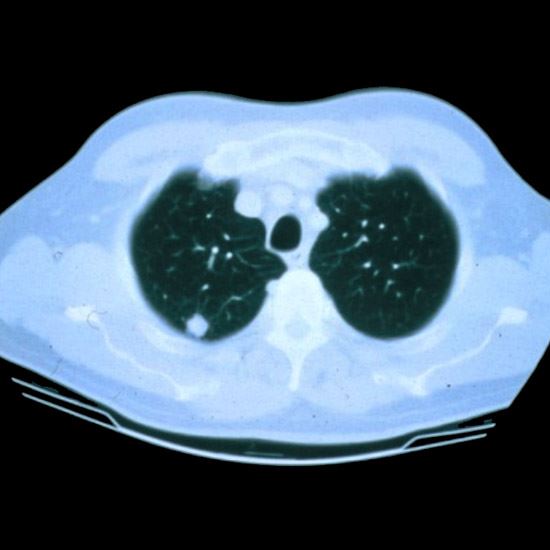

A low dose CT scan aids in finding cancer sooner and with early detection generally, more treatment options may be available.

Now more than ever, advanced screening can detect lung cancers earlier, so individuals can get better treatment outcomes. The screening utilizes a “low dose” CT scan to find any nodules especially in people who do not yet show any signs of lung cancer, but may be considered at high risk for the disease. Remember, the screening is a process, not a single test. An individual must adhere to the screening for early detection.